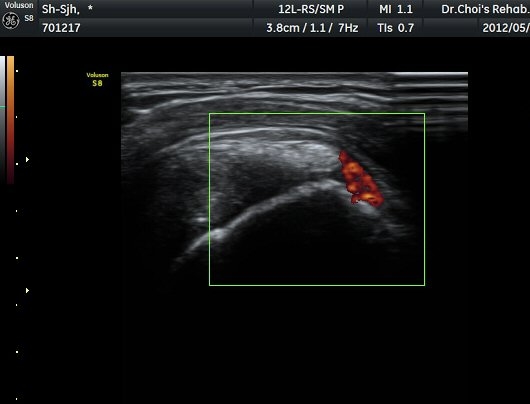

µÈ´Ù(»çÁø 3). ±Ø»ó°Ç Á¾´Ü¸é°Ë»ç»ó ±Ø»ó°Ç ºÎÂøºÎ¿¡ °í¿¡ÄÚ µ¢¾î¸®°¡ °üÂûµÇ°í(»çÁø 4, 5)

ÆÄ¿öµµÇ÷¯ °Ë»ç¿¡¼­ Ç÷·ùÁõ°¡¸¦ º¸ÀδÙ(»çÁø 6).  Ⱦ´Ü¸é°Ë»ç¿¡¼­µµ °í¿¡ÄÚ µ¢¾î¸®¿Í